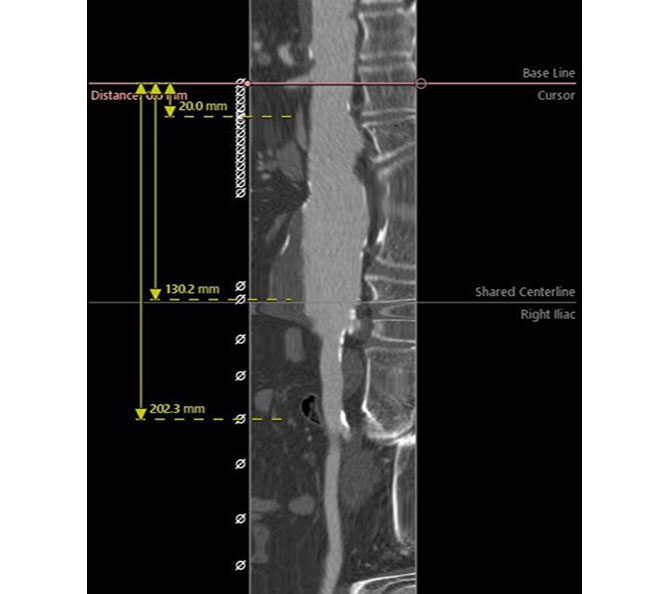

Περίπτωση 3

Άνδρας ασθενής 65 ετών με ανεύρυσμα κοιλιακής αορτής μέγιστης διαμέτρου 5,8 εκατοστών που αρχίζει αμέσως κάτω από τις νεφρικές αρτηρίες (παρανεφρικό), παχύσαρκος, με πολλαπλές συνοδές παθήσεις που αποκλείουν την ανοιχτή χειρουργική αποκατάσταση, η οποία με την σειρά της παρουσιάζει σημαντική πιθανότητα για μετεγχειρητικές επιπλοκές

Αντιμετωπίστηκε ενδαγγειακά με την τεχνική χρησιμοποίησης εξατομικευμένου μοσχεύματος τύπου Zenith με πλάγιες οπές (fenestrations), στις 2 νεφρικές αρτηρίες και την άνω μεσεντέριο αρτηρία με επιπρόσθετη ευρεία εγκοπή (scallop) για την κοιλιακή αρτηρία, το οποίο σχεδιάστηκε αποκλειστικά για την περίπτωση του